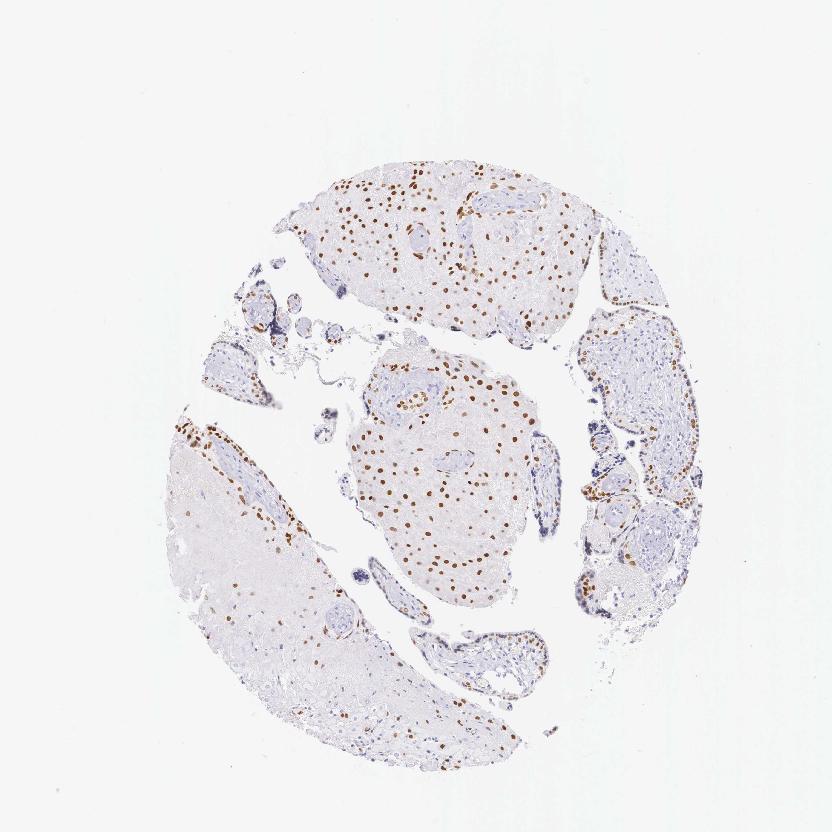

Antibody staining in the annotated cell types in the current human tissue is reported as not detected, low, medium, or high. This score is based on the staining intensity and fraction of stained cells.

Information about each individual sample is listed below, including gender, age, a tissue section image and estimated fractions of cell types. pTPM (transcripts per million) values give a quantification of the gene abundance which is comparable between different genes and samples.

Placenta sample 202 pTPM: 59.1

Cell types%

Trophoblastic cells: 45 Endothelial cells: 5 Other cell types: 50

Female, age 39

Placenta sample 203 pTPM: 62.5